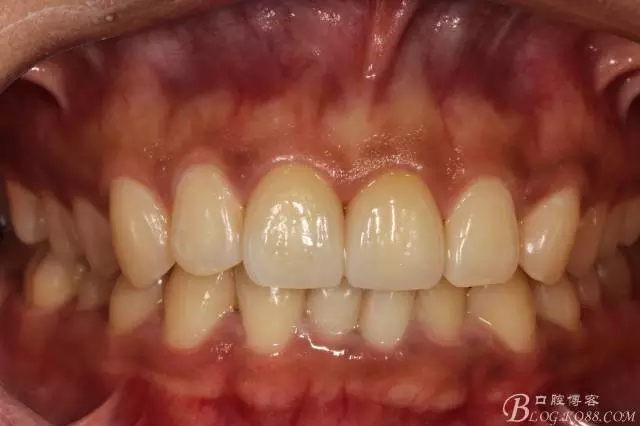

2016.1復(fù)查情況很不好,再次建議做瓷貼面并告知各自?xún)?yōu)缺點(diǎn)。這回患者同意并選擇鑄瓷貼面。

11扭轉(zhuǎn)明顯,擔(dān)心備牙過(guò)多,所以選取了一個(gè)模型,在石膏模型上先試備后,感覺(jué)還行。

備牙后11(因扭轉(zhuǎn)制牙有點(diǎn)多,還是露牙本質(zhì)了)

局部放大